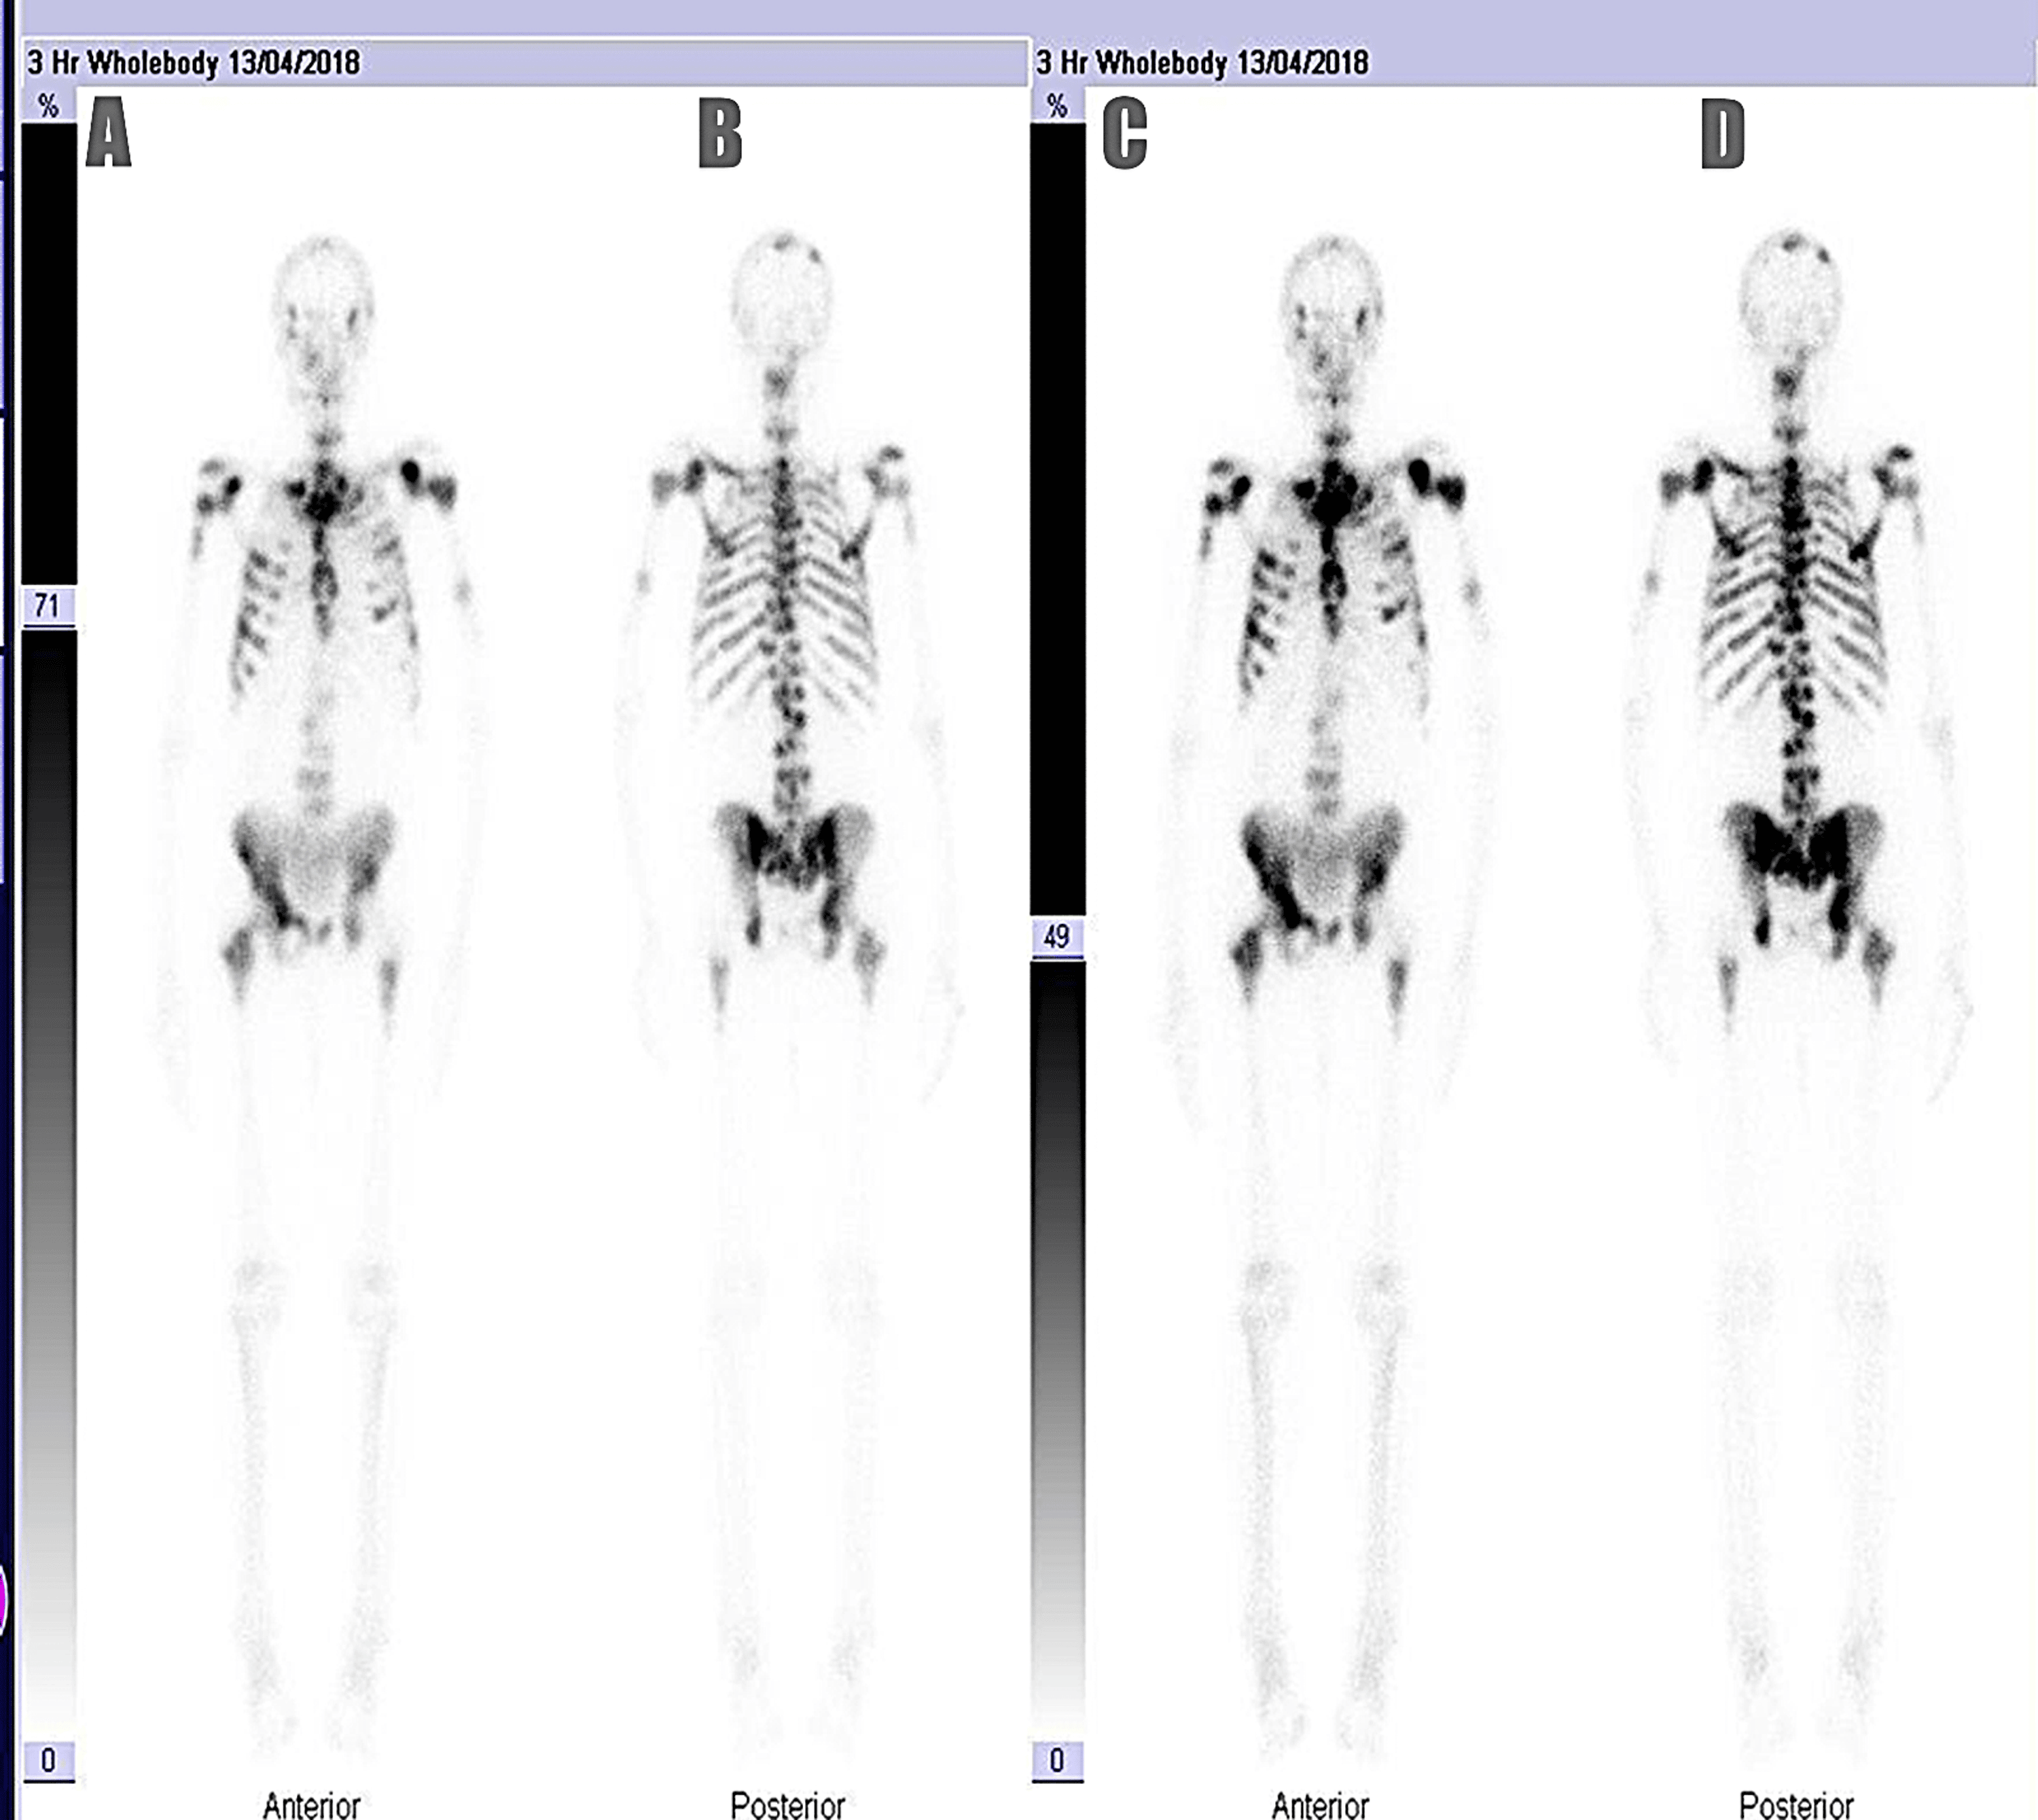

image size: 1800x1077

FIGURE 1. | The Detection of Bone Metastases in Patients with High-Risk Prostate Cancer: 99mTc-MDP Planar Bone Scintigraphy, Single- and Multi-Field-of-View SPECT, 18F-Fluoride PET, and 18F-Fluoride PET/CT | Journal of Nuclear Medicine